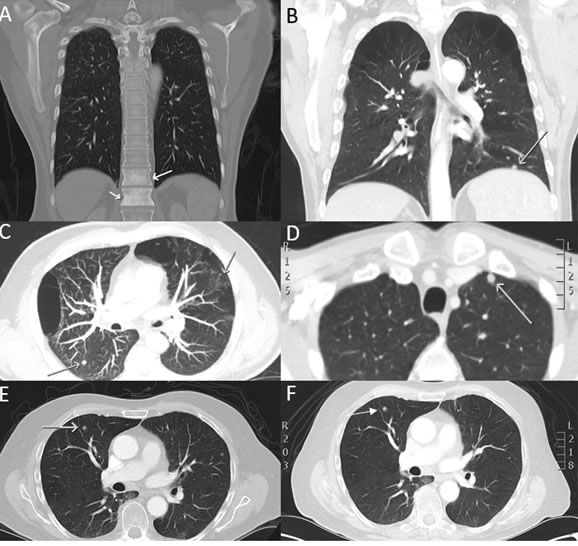

A total of 58 patients were included in this study. Patient characteristics are shown in Table 1. The median age was 60 years (range 40-87); men (n = 50), women (n = 8). The most distinctive histology was mucosal oral cavity SCC (68.1%) followed by oropharyngeal (22.4%), nasopharyngeal (6.9%) and laryngeal SCC (8.6%). The bulk of patients presented with tumour grade ranging from T4 (55.1%) to advanced nodal spread (N2A-C) (62.1%). The HPV-status was determined in all patients (n = 58) and found to be positive for HPV-16 (n = 14). DM was assessed by a multidisciplinary team (MDT) at the PAH by combining CT/PET-CT and MRI scans. 98.3% of the patients were found to be radiographically M0. CTC presence was determined from new patients upon presentation to the clinic, prior to therapy. Upon patient follow up, two patients in the study had succumbed to their disease. One patient (T4N2CM0 oropharyngeal SCC, HPV-16 positive) treated with chemotherapy (Docetaxel, cisplatin and 5-fluorouracil) died within 11 days and the other patient (T4N2BM0 supraglottic SCC) who had mildly avid FDG-PET uptake on the in the right apex of the lung died in 24 days (See Figure 4). Notably, both patients presented with CTC clusters in their blood post RosetteSep™ enrichment.

Figure 4: CT scan images of selected HNC patients presenting with suspicious HNC metastasis. Bloods were taken upon presentation of these patients to clinic and CTCs assessed. Patient presenting with A. bony metastasis B., C., D. multiple suspicious lung metastasis E., F. lung nodule which increased in size over 37 days.